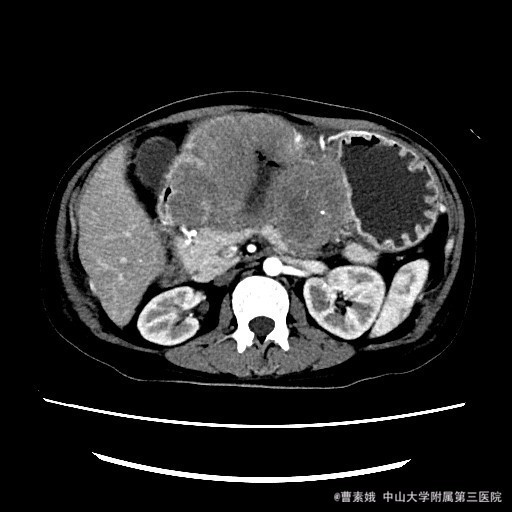

患者:女 37岁 主诉:发现腹部包块伴恶性、呕吐1月余 病史:患者平素一直有胃部不适,偶有胃痛、饱胀感不适,一直口服药物治疗,未见明显好转,1月前自觉腹部包块,并出现恶性、呕吐。呕吐为胃内容物。

查体:左上腹触及一包块,较柔软,余未特殊。 辅助检查:全腹CT平扫+增强示:胃体至胃窦部胃壁弥漫性增厚并软组织肿块,考虑淋巴瘤可能性大。

入院诊断:胃淋巴瘤(?) 治疗:诊断:胃淋巴瘤(?) 治疗:入院后(胃部肿物)送检组织镜下见胃粘膜固有层及肌层结构破坏,并见中等偏大异形淋巴样细胞弥漫浸润,局部成片分布,细胞具有异型性,可见核仁,核分裂象易见,结合免疫组化结果,符合高级别B细胞源性淋巴瘤,考虑滤泡淋巴瘤(FL3b)。组织少,肿瘤成份少,不完全排除弥漫大B细胞性淋巴瘤(生发中心亚型)。建议结合临床。排除手术禁忌症后,于腹腔镜下胃大部分切除术 。 术程顺利,患者恢复较好,建议其进一步化疗,患者表示拒绝后出院。